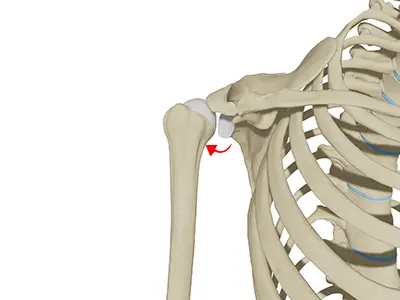

Rotator Cuff Repair

The rotator cuff is a group of 4 muscles in the shoulder joint including the supraspinatus, infraspinatus, teres minor, and subscapularis.